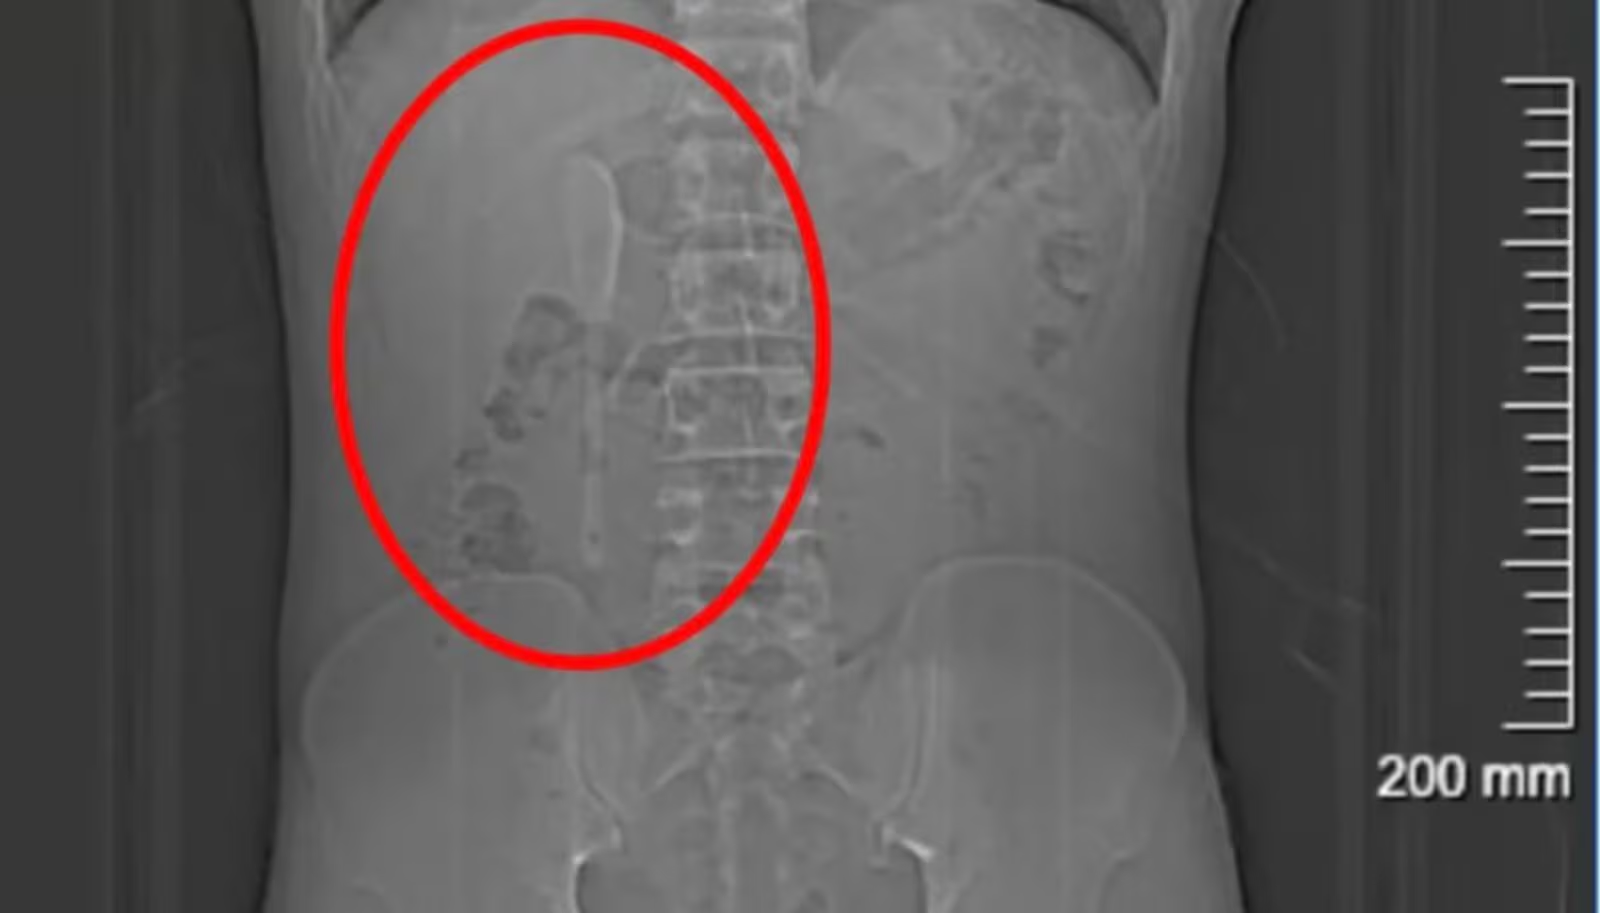

Mesmo com a colher dentro do organismo, Yan manteve sua rotina normalmente por cerca de cinco meses sem apresentar sintomas significativos. Somente em junho deste ano ele procurou ajuda médica após suspeitar ter ingerido plástico junto com uma refeição delivery. Exames revelaram então a presença da colher de 15 centímetros presa numa região delicada do intestino.

A remoção da colher foi considerada complexa pelos médicos devido à superfície lisa e escorregadia do utensílio e ao risco elevado de perfuração intestinal durante o procedimento. A cirurgia endoscópica durou aproximadamente nove horas e exigiu o uso combinado de dois tipos diferentes de pinças para puxar cuidadosamente a colher até o estômago antes da extração completa.Após o sucesso na operação, Yan recebeu alta hospitalar demonstrando alívio por finalmente descobrir a causa dos incômodos abdominais antes que surgissem complicações mais sérias.